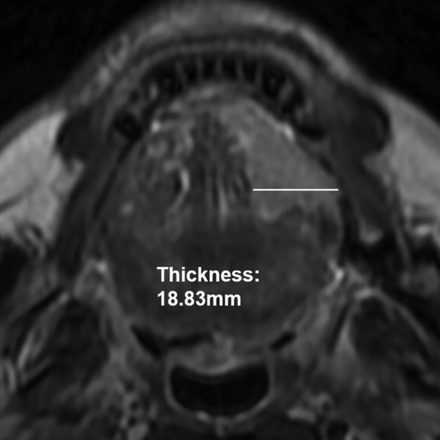

Tumor thickness and tumor volume were measured by using axial T2WI according to methods taken from previous studies.3,5⇓–7 Tumor thickness was defined as the distance from the tumor surface to the deepest point of invasion. Meanwhile, after the lesion-involving area in each section was delineated by using an operator-defined ROI, the tumor volume was obtained from the sum of the areas multiplied by the section interval. The methods used for the MR imaging–based measurement of tumor thickness and tumor volume are shown in Figs 2 and 3, respectively. Imaging analysis was performed independently by 2 dedicated head and neck radiologists blinded to the pathologic results. The mean values of their measurements were calculated for further statistical analysis.

Tumor thickness was measured by the distance from the tumor surface to the deepest point of invasion.